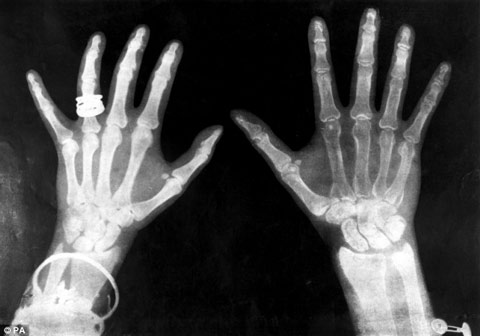

Tia X là phát minh tạo tiến bộ vượt bậc trong y khoa. Trên ảnh là hình chụp X-quang của vua George và hoàng hậu Mary năm 1896.